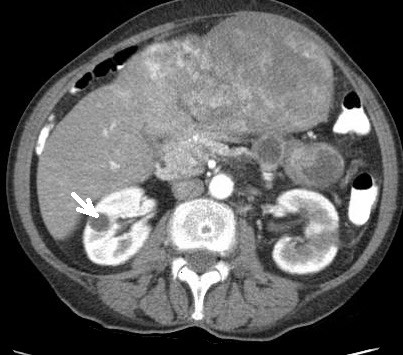

2930. Изменение, указанное стрелкой на изображении, соответствует